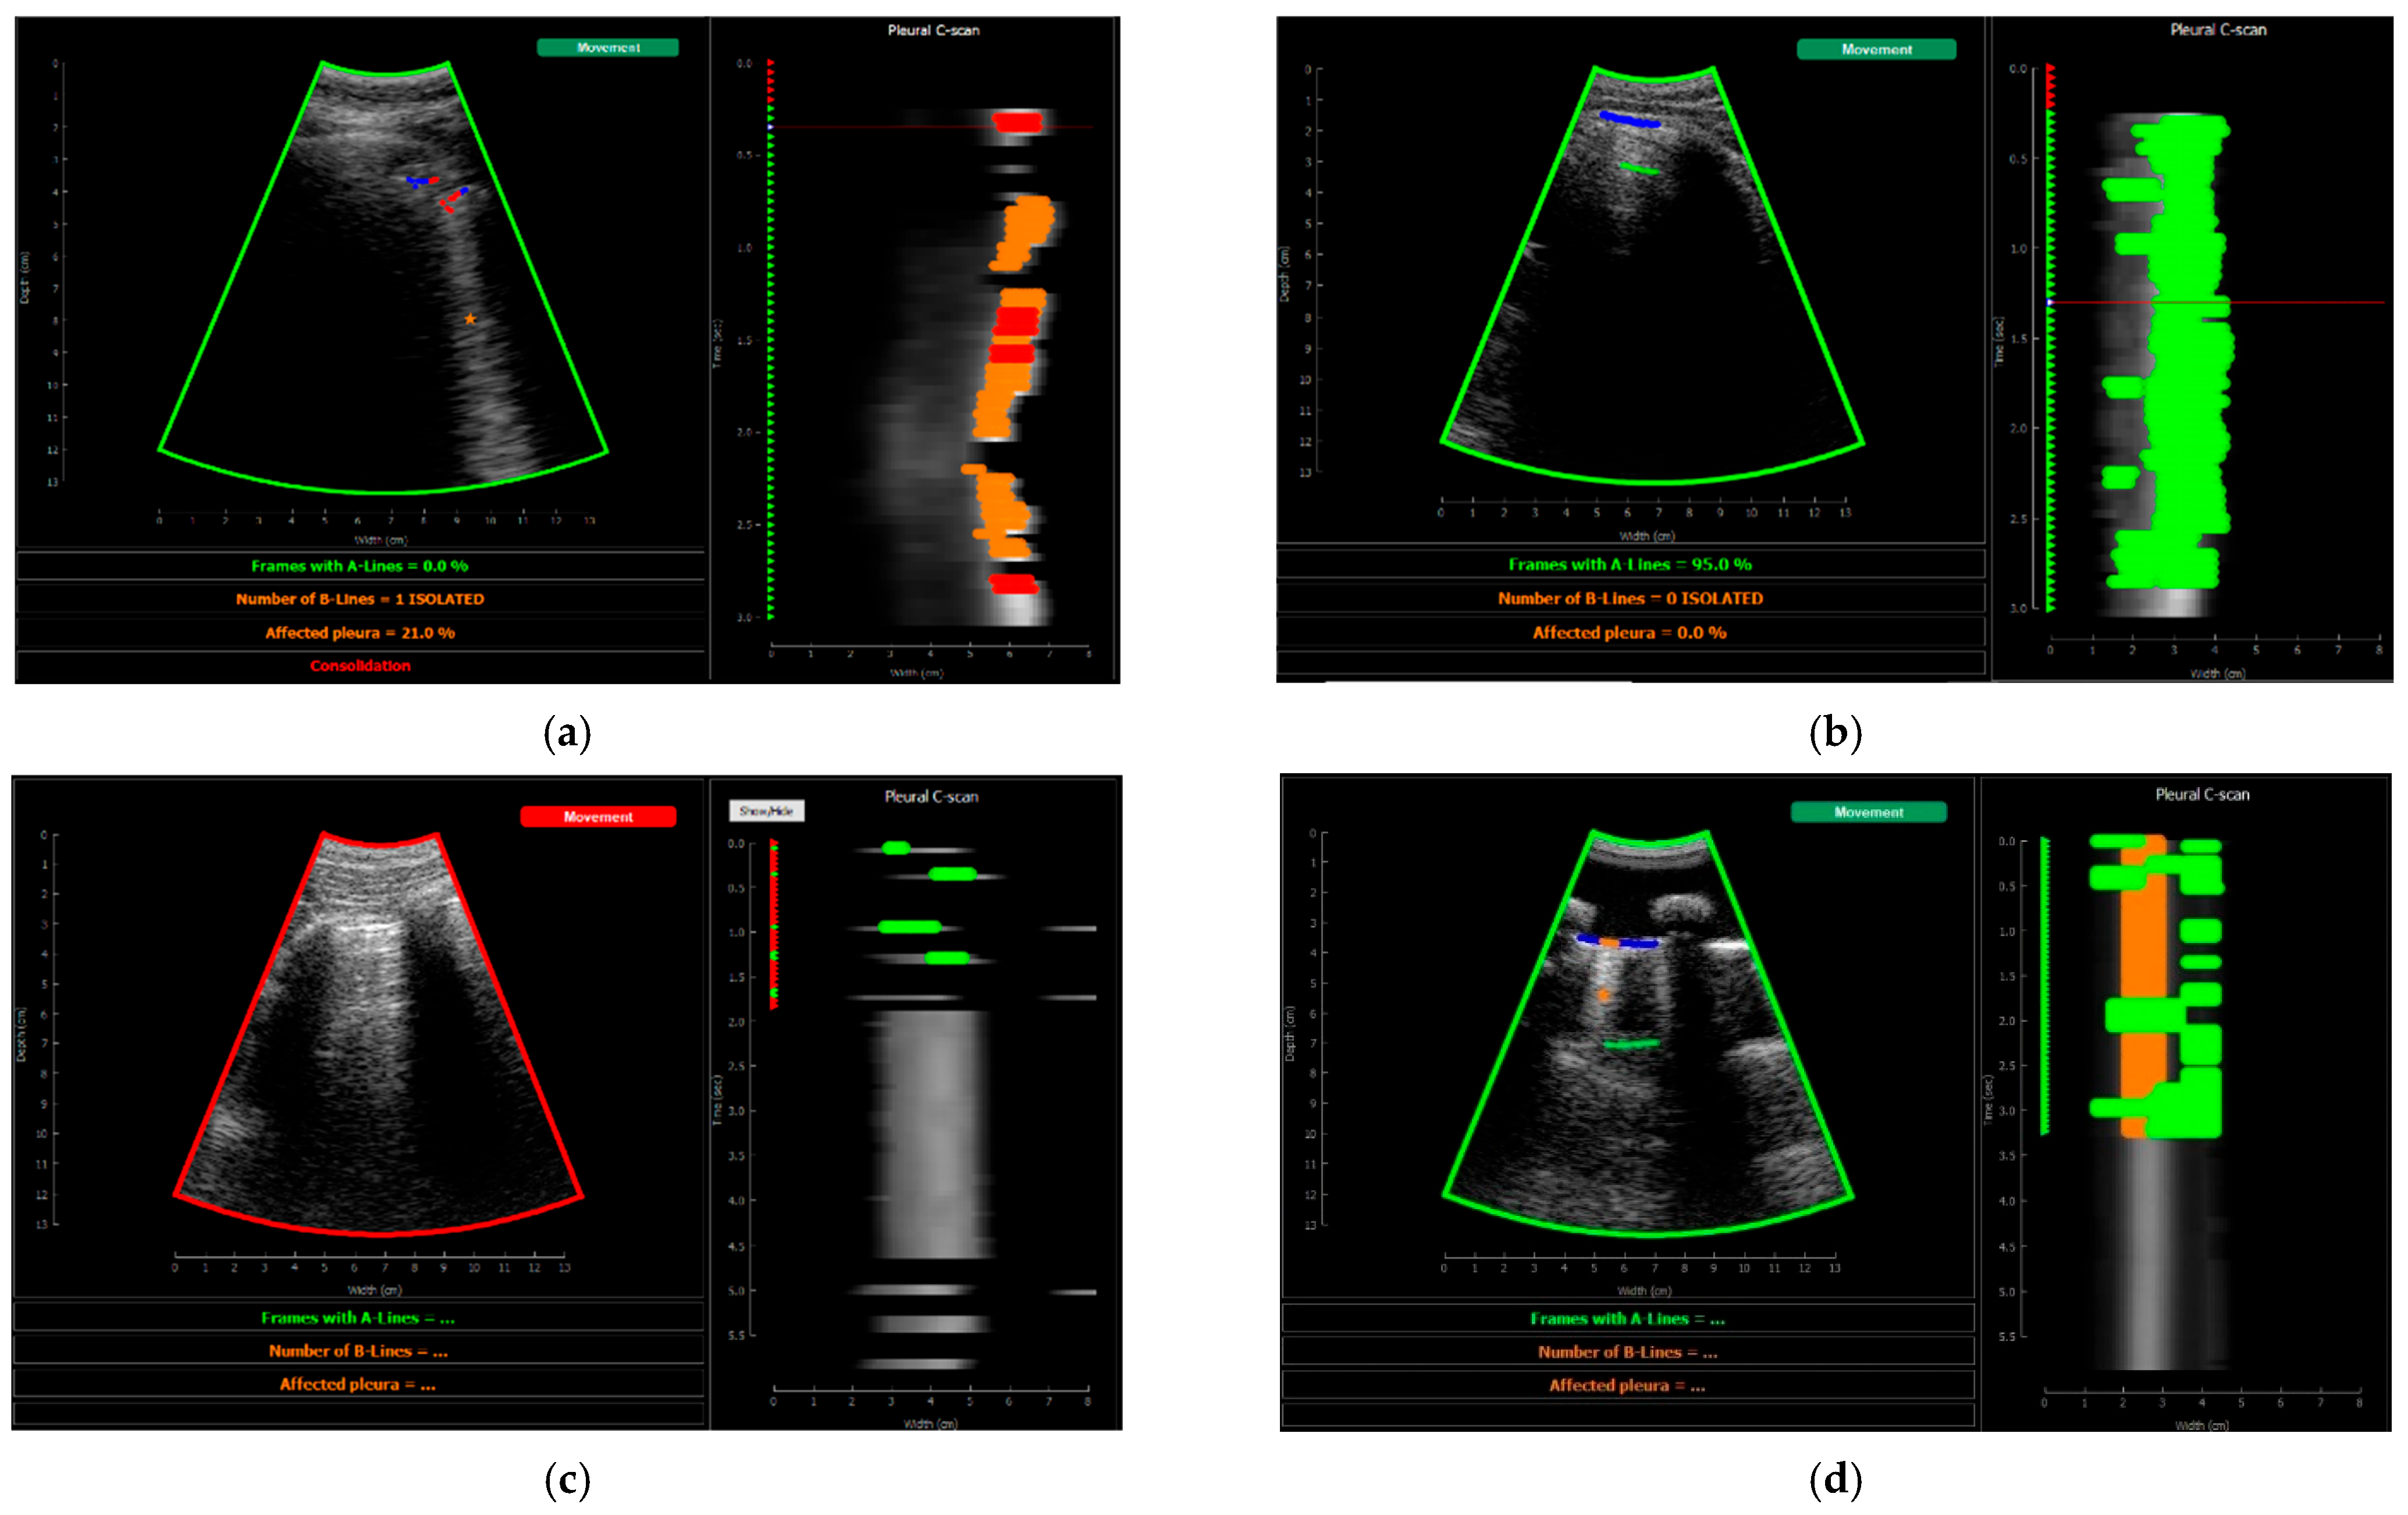

Figure 16 shows several examples of the screen of the implemented software in operation explained in Section 2.5.4.

Figure 16.

Application visualization sample: (a) B-lines (orange) and consolidation (red) detection; (b) normal lung with A-lines (green); (c) probe movement detected; (d) B line (orange) and A-line (green) deteccion on a Lung phantom. On the right of each image the C-scan image is shown.

Figure 13 shows the screen shown to the user. On the left, the acquired sector-scan images are shown in real-time, with several overlays coming from the processing algorithm. When the image is valid for being evaluated, the contour of the image turns green, and so the label “movement” on the upper right corner. If the image fails to pass any of this criterion, the contour line turns red, and so the labels that triggered the event. Therefore, the physician can freely move the probe on the patient chest until theses indications turn green, and then hold probe steady to acquire a video of 3 s that will be saved for each of the 12 regions to be examined according to the protocol.

This image also overlays, in real-time, the findings of the neural network. The pleura is marked with blue points, A-Lines with green points, B-Lines with orange points, and consolidations with red points. Furthermore, a series of statistics and messages are shown in the lower part of this image: the percentage of frames with A-Lines in the last 6 s; the number of isolated B-Lines, calculated as the sub-regions with an average 6 dB drop in the angular direction within the region where B-Lines were detected; the percentage of the affected pleura calculated as the number of scan lines affected by B-Lines over the total number of scan lines where the pleura was detected; and a label in red indicating that a consolidation when present.

On the right of the screen, an image we refer as pleura C-scan is shown. The C-Scan is a type of image widely used in Non-Destructive Testing (NDT) applications where B-scan images are acquired while the probe is moving and a visual representation of the whole component is needed [33]. For each image line within the B-Scan, the maximum amplitude is obtained within a gate at some depth, which assembles an ensemble image that can be interpreted like a top view of the component, with defects information at a certain depth. We adapted this concept using a gate at the depth of the pleura, obtained from the pleura mask given by the model, and substituting the mechanical movement of the probe in an NDT scan, by the time index in the acquired video. Therefore, each horizontal line in the pleura C-Scan correspond to a frame in the video, and it shows the brightness of the pleura line along the horizontal dimension of the image. At each of these lines, landmarks with the previously defined colours are also plotted. As the video progresses, the C-Scan image is constructed frame by frame from top to bottom and, at the end, all the relevant information of the video is condensed in only one image. The presence of A-Lines, B-Lines, and consolidations and their extension with regard to the pleura width can be appreciated, and also the pleura sliding effect as the indications move laterally during the scan. Furthermore, these images could be saved for each acquired region in the chest and shown in a single panel that depicts the global condition of the lung in a single view, without the need to review each of the acquired videos for the whole examination, which could help to reduce time during follow up of patients.